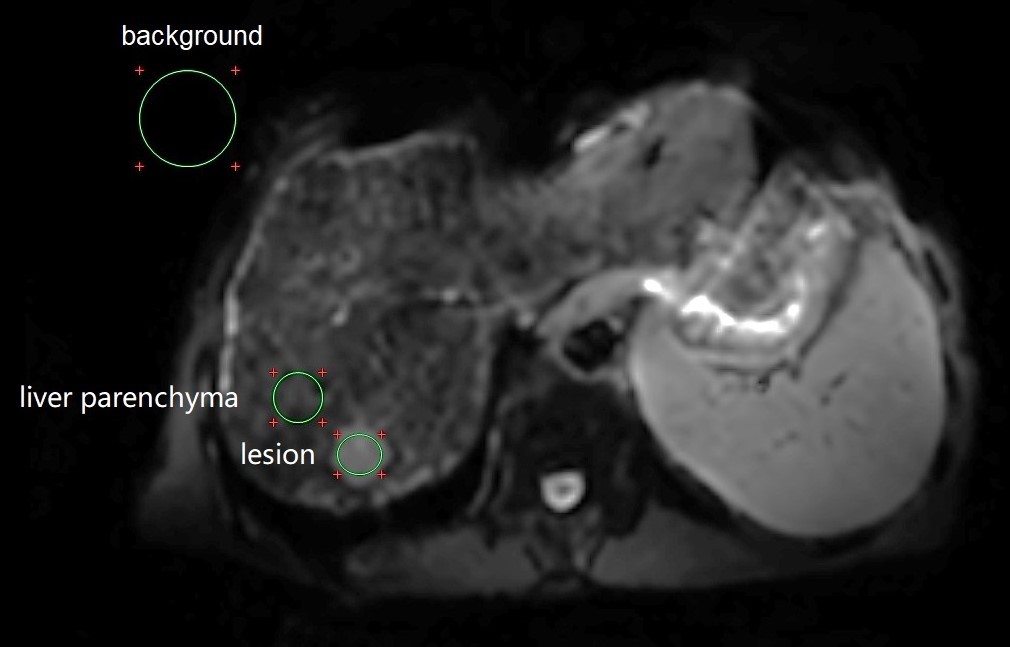

Overall image quality was independently reviewed by two radiologists with more than 3 years of experience in abdominal imaging using a 5-point scale4. Quantitative liver SNR and lesion contrast-to-noise ratio (CNR) were calculated using the vender provided workstation (ADW 4.4; GE Healthcare, Milwaukee, CA, USA). The liver SNR was defined as the mean signal of liver dividing by the standard derivation (SD) of background noise. The lesion CNR was calculated with dividing the signal difference between lesion and liver by the background SD. Figure 1 showed an example definition of the ROIs . DWI derived apparent diffusion coefficient (ADC) map was generated with a mono-exponential model by the vendor provided workstation.

Fig. 1. An example DWI (b = 800 s/mm2) image of a representative hepatocellular carcinoma patient was used to show the ROI definition. Three kinds of ROIs were used in this study, including focal liver lesion, liver parenchyma, and background.